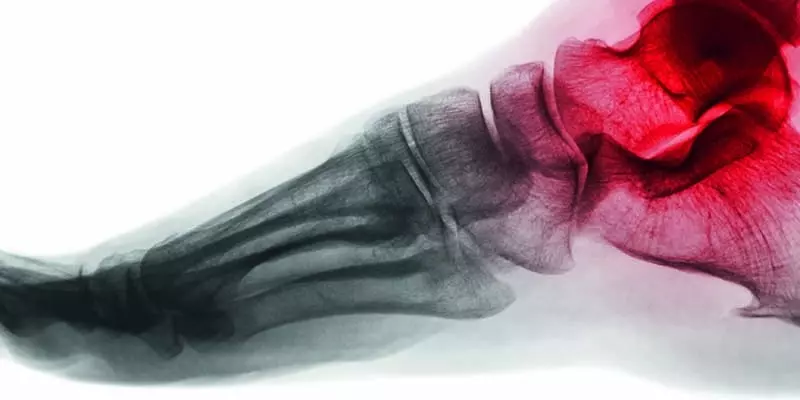

Złamanie dystalnej nasady kości promieniowej jest najczęściej występującym złamaniem kończyny górnej. Złamania w tej okolicy dotyczą 40% kobiet oraz 13% mężczyzn. Budowa kompleksu ręka – przedramię jest na tyle specyficzna, że zdecydowana większość

energii podczas upadku z próbą podparcia kumuluje się na kości promieniowej. Szacuje się, że co piąte złamanie dotyczy omawianej lokalizacji. Inne statystyki mówią, że występują one u 2 osób na 1000 w ciągu roku.

Zdecydowanie najczęściej występującym mechanizmem złamania jest próba ochrony wyprostowaną ręką przed upadkiem. Efektem upadku jest zwykle złamanie dystalnej nasady kości promieniowej. Złamania występują częściej u kobiet po menopauzie. Urazowi sprzyjają istotne czynniki ryzyka, takie jak osteoporoza, choroby układowe czy procesy rozrostowe, które znacznie zwiększają prawdopodobieństwo wystąpienia złamania. Skrajnie rzadko występują złamania „powolne” w wyniku przeciążenia.